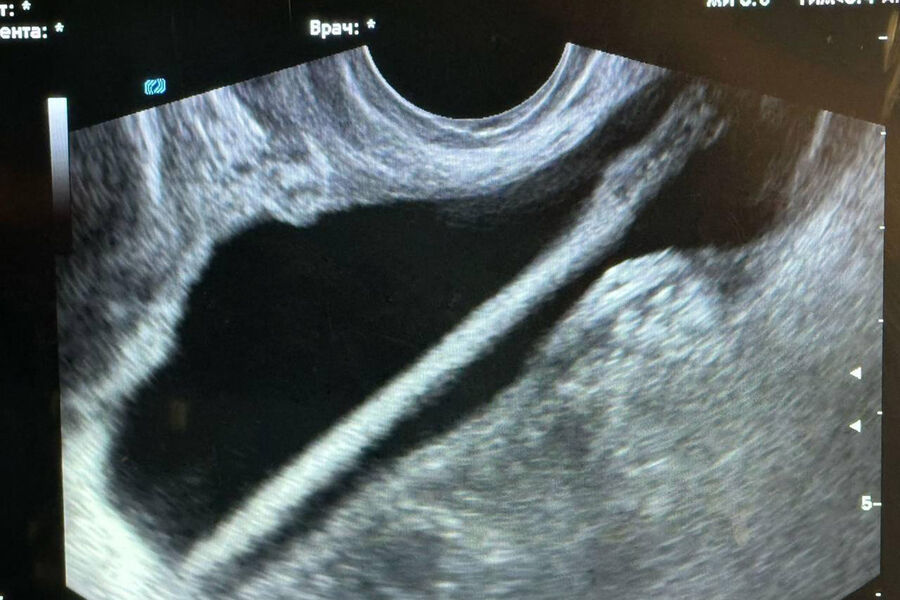

Инцидент произошел в Красногорской больнице. Пациентка обратилась в приемное отделение и рассказала, что ввела себе в мочевой пузырь через мочеиспускательный канал косметический карандаш. После обследования женщину госпитализировали в урологическое отделение.

С помощью эндоскопа хирурги извлекли инородное тело. Оперативное вмешательство прошло без осложнений, пациентку уже выписали домой. Однако медики предупредили, что подобные эксперименты могут привести к травмам, воспалениям и тяжелыми инфекциям.